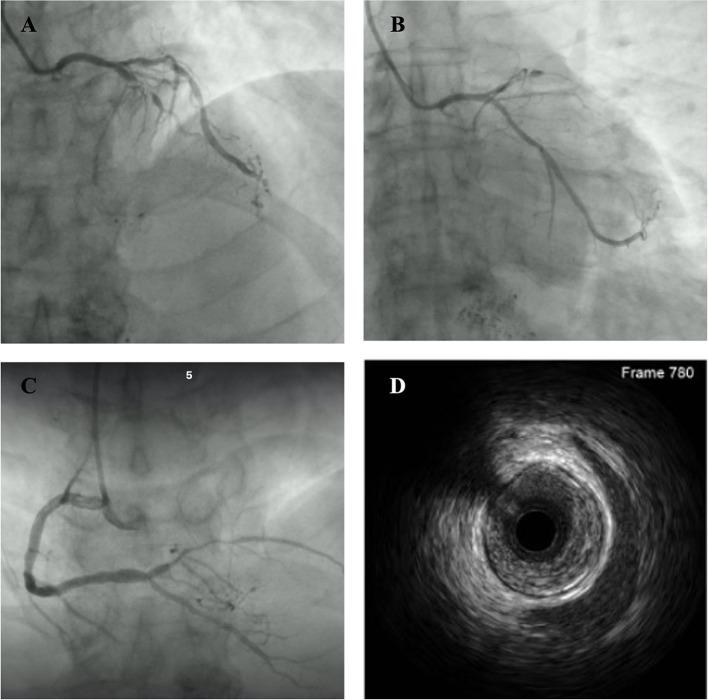

Coronary artery spasm (CAS) may induce lethal ventricular arrhythmia due to severe and prolonged vessel constriction. Tyrosine kinase inhibitors are associated with the occurrence of CAS. Optimal medical treatment is the first-line therapeutic option for the management of CAS, whereas patients who experienced aborted sudden cardiac death (SCD) may benefit from implantable cardioverter-defibrillator (ICD) implantation. We report a case of a 63-year-old Chinese man receiving tyrosine kinase inhibitor treatment for liver cancer who presented with recurrent chest discomfort and syncope with an elevation of high-sensitivity troponin T. Emergent coronary angiography showed sub-total occlusion of the left anterior descending artery without other signs of CAS. Percutaneous transluminal coronary angioplasty with a drug-coated balloon was performed successfully with the guidance of intravascular ultrasound. After 5 months, the patient returned to the emergency room for chest discomfort and another episode of syncope. The electrocardiogram showed ST-segment elevation in the inferior and V5-V6 leads compared to the previous event. Coronary angiography was repeated immediately and showed significant luminal stenosis at the midportion of the right coronary artery (RCA), whereas, after administration of intracoronary nitroglycerine, a remarkable recovery of RCA patency was noticed. A diagnosis of CAS was made, and soon after that, the patient rapidly developed ventricular arrhythmia in the coronary care unit. After successful resuscitation, the patient recovered completely and received long-acting calcium channel blockers as well as nitrates therapy. ICD implantation was performed considering the high risk of recurrence of life-threatening ventricular arrhythmia. During the follow-up period, the patient has been free of angina, syncope, or ventricular arrhythmia, and ICD interrogation showed no ventricular tachycardia or ventricular fibrillation. We first reported the case of a patient with CAS induced by regorafenib treatment complicated with severe atherosclerotic coronary disease who survived from sudden cardiac arrest. ICD implantation is indicated in patients who experienced aborted SCD for the prevention of the next lethal ventricular arrhythmia.

冠状动脉痉挛(CAS)可能由于严重且持续的血管收缩而诱发致命性室性心律失常。酪氨酸激酶抑制剂与CAS的发生有关。最佳药物治疗是CAS管理的一线治疗选择,而经历过心脏性猝死(SCD)未遂的患者可能受益于植入式心脏复律除颤器(ICD)植入。我们报告一例63岁中国男性,因肝癌接受酪氨酸激酶抑制剂治疗,出现反复胸痛和晕厥,高敏肌钙蛋白T升高。急诊冠状动脉造影显示左前降支次全闭塞,无其他CAS迹象。在血管内超声引导下成功进行了药物涂层球囊经皮冠状动脉腔内血管成形术。5个月后,患者因胸痛和再次晕厥返回急诊室。心电图显示与上次事件相比,下壁及V5-V6导联ST段抬高。立即重复冠状动脉造影,显示右冠状动脉(RCA)中段明显管腔狭窄,而在冠状动脉内给予硝酸甘油后,RCA通畅情况明显恢复。诊断为CAS,此后不久,患者在冠心病监护病房迅速发生室性心律失常。成功复苏后,患者完全康复,并接受长效钙通道阻滞剂以及硝酸盐治疗。考虑到危及生命的室性心律失常复发风险高,进行了ICD植入。在随访期间,患者未再出现心绞痛、晕厥或室性心律失常,ICD程控显示无室性心动过速或心室颤动。我们首次报告了一例由regorafenib治疗诱发CAS并合并严重动脉粥样硬化性冠状动脉疾病的患者,该患者从心脏骤停中存活。对于经历过SCD未遂的患者,建议植入ICD以预防下一次致命性室性心律失常。